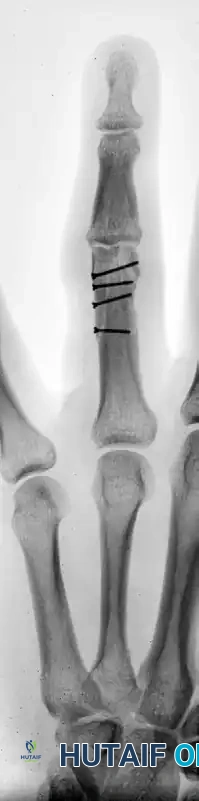

Postoperative Result:

The screw heads must be countersunk or carefully selected to ensure a low profile. The following radiographs demonstrate successful anatomic reduction and fixation.

FIGURE 67-41 D: Postoperative AP radiograph showing anatomic restoration of the joint line.

FIGURE 67-41 E: Postoperative oblique radiograph confirming flush seating of the minifragment screws.

FIGURE 67-41 F: Postoperative lateral radiograph demonstrating restoration of the sagittal alignment. Note that the small screw heads do not interfere with collateral ligament function.